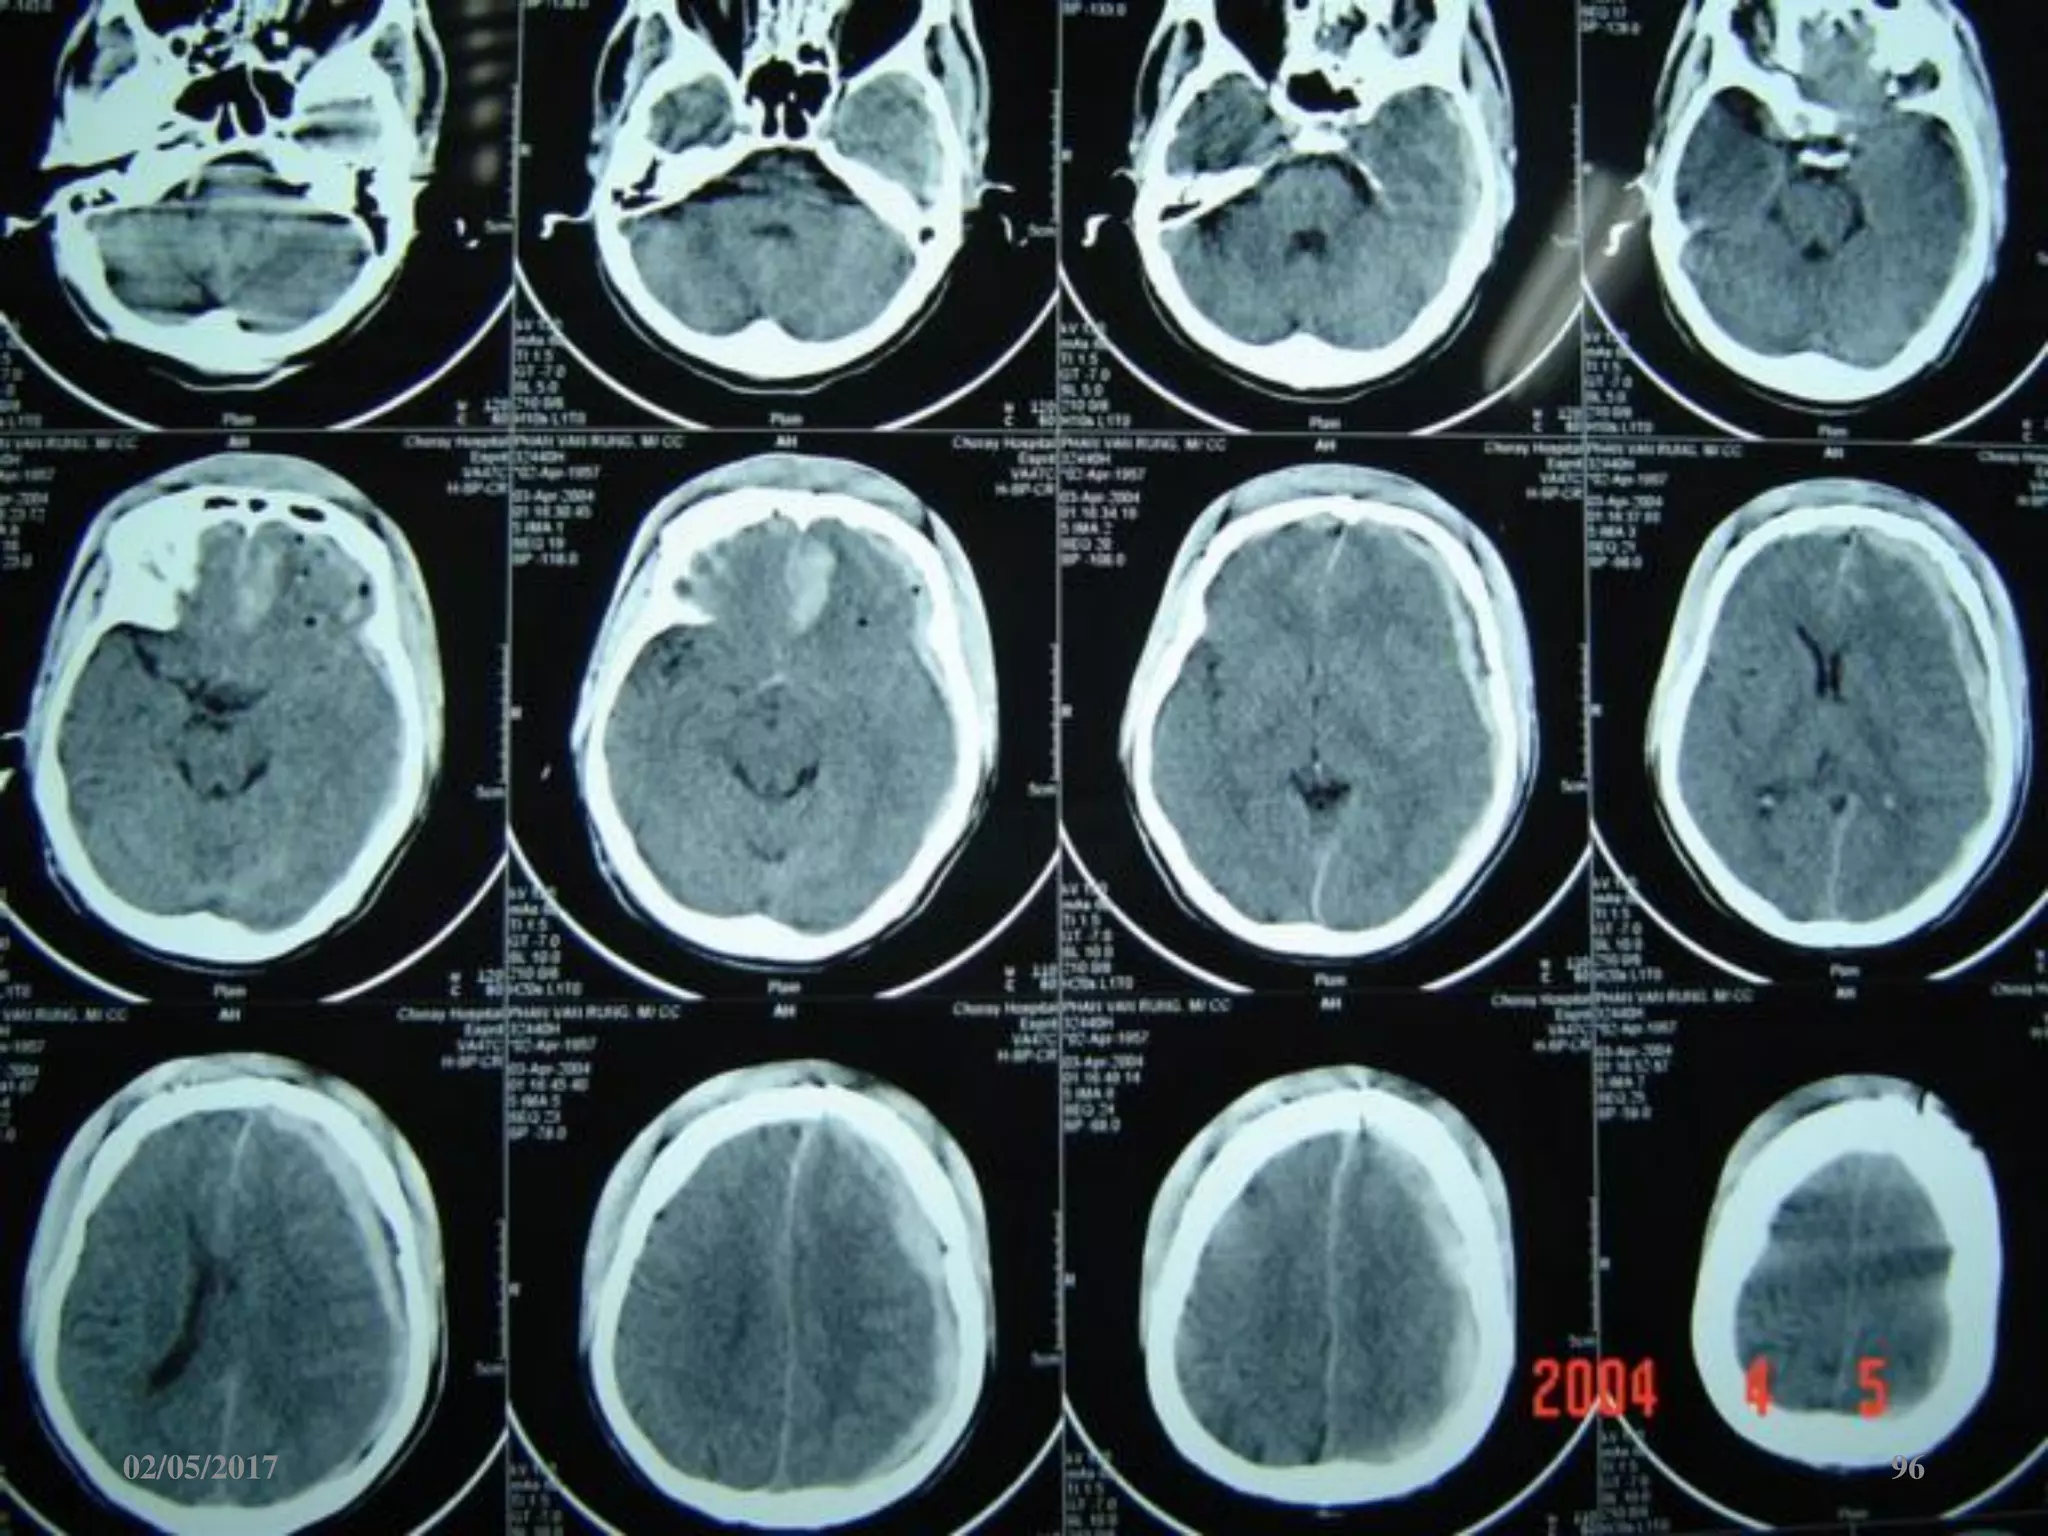

Máu tụ dưới màng cứng cấp

 Ngoài trục, hình liềm,

tăng đậm độ

 Vượt qua được các

khớp sọ

 Thường kèm dập não

02/05/2017 54

Phù não

• Giảm đậm độ lan tỏa.

• Mất ranh giới chất

trắng-xám.

• Xóa các rãnh não-bể

não.

• Não thất 2 bên nhỏ.